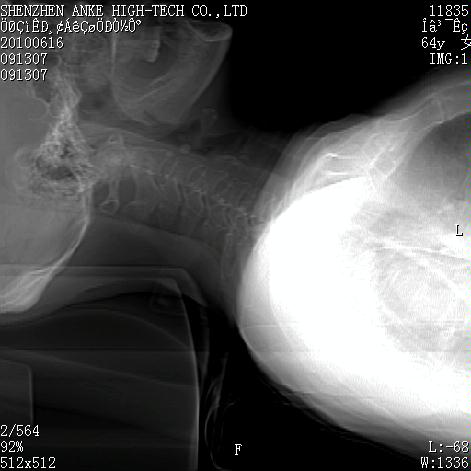

标题: CT27132:患者女,64岁,颈部及全身多处包块,现觉吞咽困难4 [打印本页]

标题: CT27132:患者女,64岁,颈部及全身多处包块,现觉吞咽困难4

右侧甲状腺占位,肿瘤可能性大,癌

右侧甲状腺癌伴右颌下腺淋巴结转移

右侧甲状腺癌伴淋巴结转移

右侧甲状腺癌伴淋巴结转移可能性大

右侧甲状腺癌伴淋巴结转移可能性大。

右侧甲状腺癌伴右颌下腺淋巴结转移!建议增强!